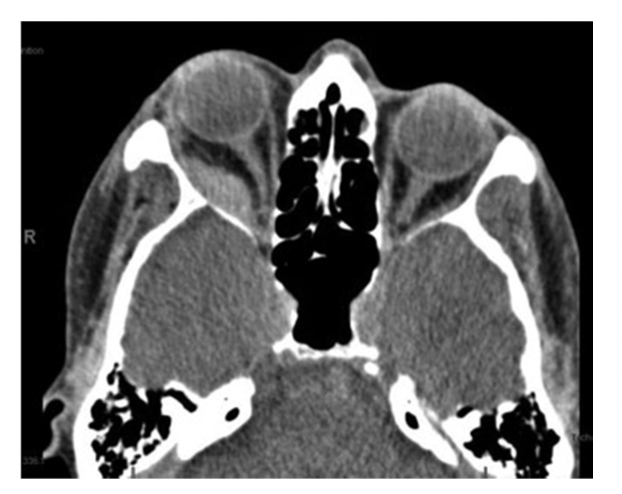

Opgave 2-1

En 53-årig mand henvender sig på skadestuen, efter han i forbindelse med løft af tung dør snubler og slår

højre ansigtshalvdel ned i en bordkant. Forud for ulykkestilfældet har patienten ikke fejlet noget med øjnene.

Patienten angiver smerter omkring højre øje, kvalme og sløret syn.

Objektivt findes visus på 1/60 højre øje og 6/6 på venstre øje. Der er hævelse og misfarvning omkring højre

øje, samt højresidig exophthalmus og hæmoragisk chemosis. (se billede). Motiliteten er indskrænket på højre

øje i alle blikretninger og normal på venstre. Højre pupil er dilateret og trægt lysreagerende.

Hvilket af nedenstående udsagn er mest korrekt?

A: Du bestiller først en CT-scanning af cerebrum for at udelukke basis cranii fraktur

B: Du bestiller først en CT-scanning af orbita for at udelukke blow-out fraktur og øvrige

ansigtsfrakturer

C: Du sender en henvisning til øjenafdelingen mhp subakut tilsyn og indlægger patienten obs commotio

D: Du kontakter vagthavende neurolog, da du primært mistænker traumatisk oculomotoriusparese

E: Du kontakter først øjenafdelingen mhp akut tilsyn, da synet er truet

Opgave 2-2

Basisoplysninger fra delopgave 1:

Du ser en 53-årig mand med stumpt traume mod højre øje. Patienten angiver smerter omkring højre øje,

kvalme og sløret syn. Objektivt finder du højresidigt periorbitalt hæmatom, kraftigt nedsat syn,

exophthalmus, trægt lysreagerende pupil og indskrænket motilitet på højre øje. Du beslutter fejlagtigt at

bestille en CT-scanning før du kontakter en øjenlæge (se billede).

Med udgangspunkt i kliniske fund og CT -scanning: Hvad er den mest sandsynlige diagnose?

A: Blow-out fraktur

B: Retrobulbær hæmoragi

C: Perforation af bulbus

D: Basis cranii fraktur

E: Glaslegemeblødning